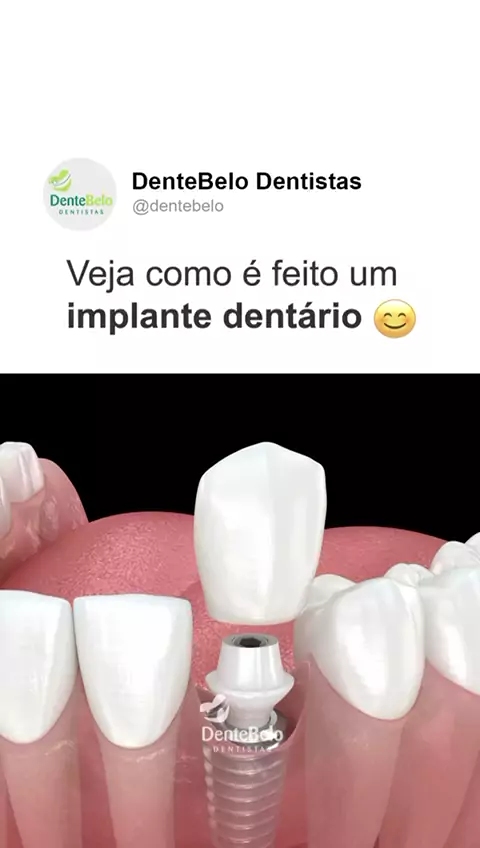

Como é feito um implante dentário? Na DenteBelo, realizamos a instalação de implantes dentários e a colocação da coroa com precisão e cuidado, devolvendo não só a estética do seu sorriso, mas também a sua qualidade de vida. 📲 Agende a sua avaliação e descubra como podemos transformar o seu sorriso!